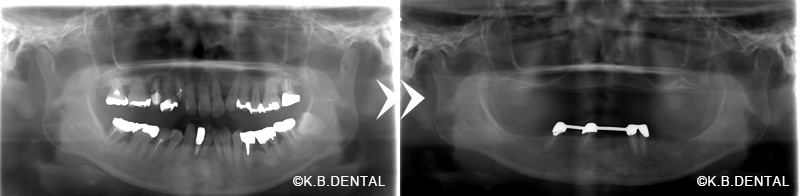

インプラント4本によるインプラントオーバーデンチャー

レントゲン:インプラントオーバーデンチャー

嘔吐反射が酷くブラッシングなどのセルフケアが難しい症例です(インプラントと義歯内面のマグネットで無口蓋金属床義歯ノンクラスプライプを維持しています)。

保存可能な歯牙は可及的に残し、クラスプと呼ばれる歯にかけるバネを使用しないため、残存歯の感覚も残しながらインプラントオーバーデンチャーによる咬合負担も可能にした症例。

咬合調整により天然歯と義歯の被圧変異量の差を考慮した調整が必要なため、装着時に細かい調整が必要ですが、長期的に安定した状態を得ることができます。

また義歯は外して義歯洗浄剤を使用し、残存歯とインプラント部は前方に集中しているため、嘔吐反射の患者さんでも手入れが容易でメンテナンスしやすい構造となっております。

年齢/性別 50代男性

治療期間 約6ヶ月

費用 約200万円(税別)